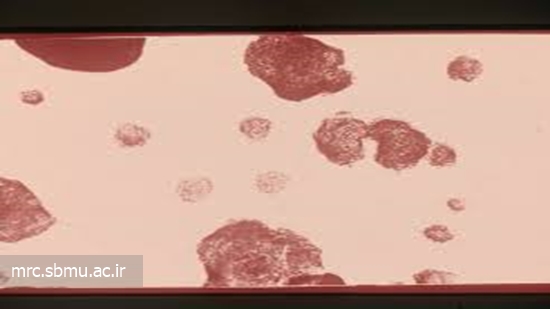

در سال گذشته دو بیمار مبتلا به سویه جدید حدواسط از توبرکلوزیس در کشور کنیا شناسایی گردیدند. این گونه که تحت عنوان pre-XDR-TB( مرحله پیش از سل حاد شدید ) شناخته شده است،  به نوعی از داروهای موجود برای درمان سل مقاوم به چند دارو ( MDR-TB) مقاوم می باشد و درصورتی که تحت درمان قرار نگیرد قابلیت تبدیل شدن به عفونت هایی با درجات خطرناک تر که تحت عنوان  XDR-TB شناخته می شوند را دارد.